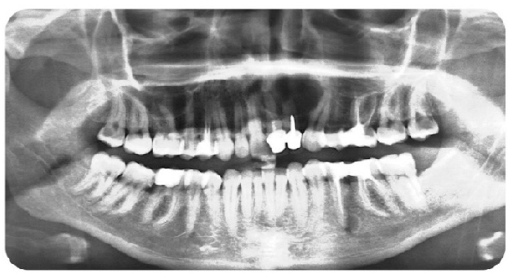

Endodontic Treatment: Challenges and Difficulties of Access Cavities -- Case Series

El Kharroubi Soukaina, Dhoum Sara, Doumari Bouchra, Drouri Sofia, Laslami Kaoutar and El Ouazzani Amal. 22(6): 38-47.